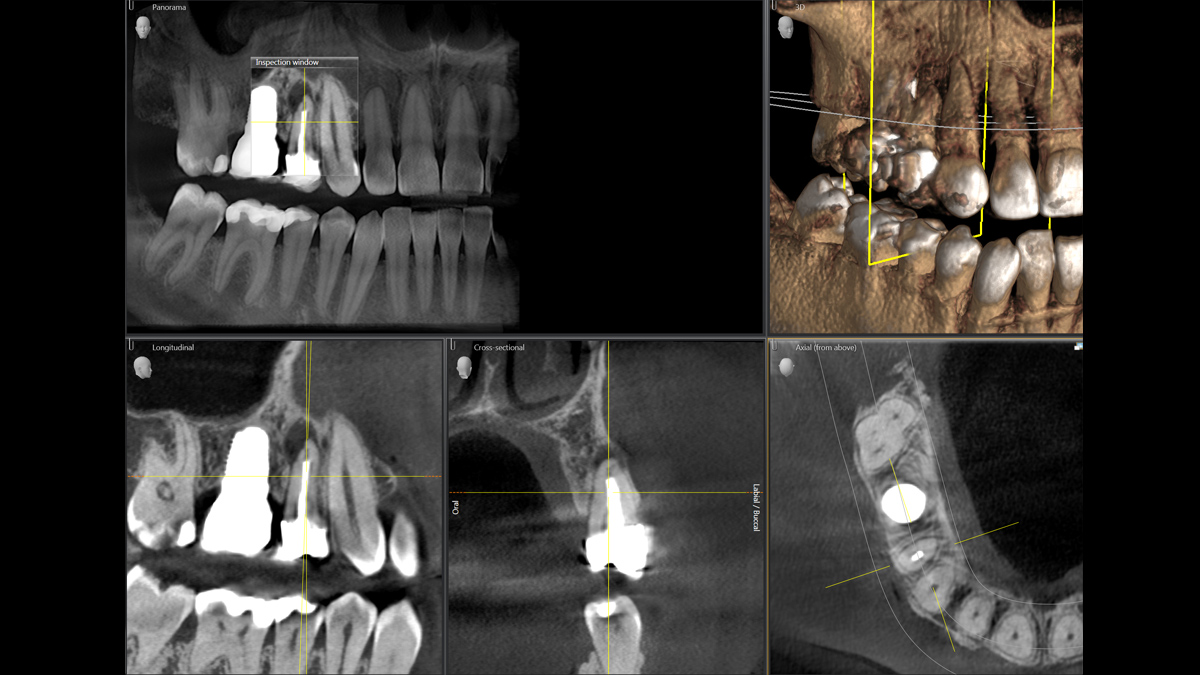

La tecnología 3D se está estableciendo cada vez más en los consultorios dentales en todo el mundo. Para diagnósticos más precisos y explicaciones del tratamiento, los rayos X en 3D ofrecen varias ventajas. Ya sea para dientes superpuestos, recorridos inesperados de los canales de los nervios, raíces ocultas o anomalías de las articulaciones temporomandibulares, las imágenes en 3D tienen un valor inestimable para un gran número de diagnósticos.

Orthophos SL 3D ofrece una gran variedad de opciones para satisfacer estas necesidades: diferentes tamaños de volumen donde elegir, modos HD/SD/Dosis bajas de radiación y un software inteligente e intuitivo para aprovechar al máximo las imágenes obtenidas y vincularlas directamente al tratamiento.

Galería de muestra de imágenes panorámicas 3D

Orthophos SL 3D en la práctica